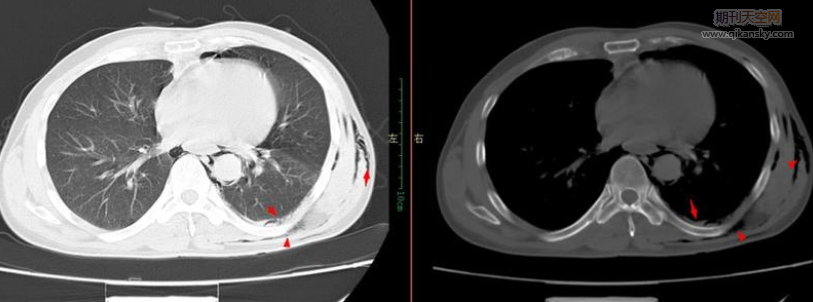

圖像采集主要通過CT、MRI、PET-CT等掃描技術獲得,CT因其具有較高的空間分辨率和灰度對比度,能有效分析腫瘤和淋巴結的形狀、密度、紋理等特征,而廣泛的而應用在肺結節良惡性鑒別[2]。

傳統的CT掃描對典型的良惡性肺結節診斷精確,但對于不典型的肺結節,例如肺小結節,傳統的CT掃描圖像特異性較低,白春學[8]設計提出肺結節的高通量特征為:肺結節的大小、形狀、密度與強化程度、邊緣毛刺程度等。形態特征指肺結節的大小和規則程度等。Peikert 等[9]經利用LASSO COX回歸模型篩選出 7 個量化的影像組學特征,在肺結節良惡性鑒別中,特異性為0.856,敏感性為0.9。Chen等[10]采用影像組學分析方法構建的分類器對于鑒別良惡性肺 結節表現出的敏感性 92. 9% ,特異性為 72. 7,準確性為 84. 0% 。Choi等[11]在低劑量 CT 中比較了LASSO COX回歸模型與ACR 研究的Lung - RADS 系統,結果表明 LASSO COX模型具有更高的敏感性和特異性。